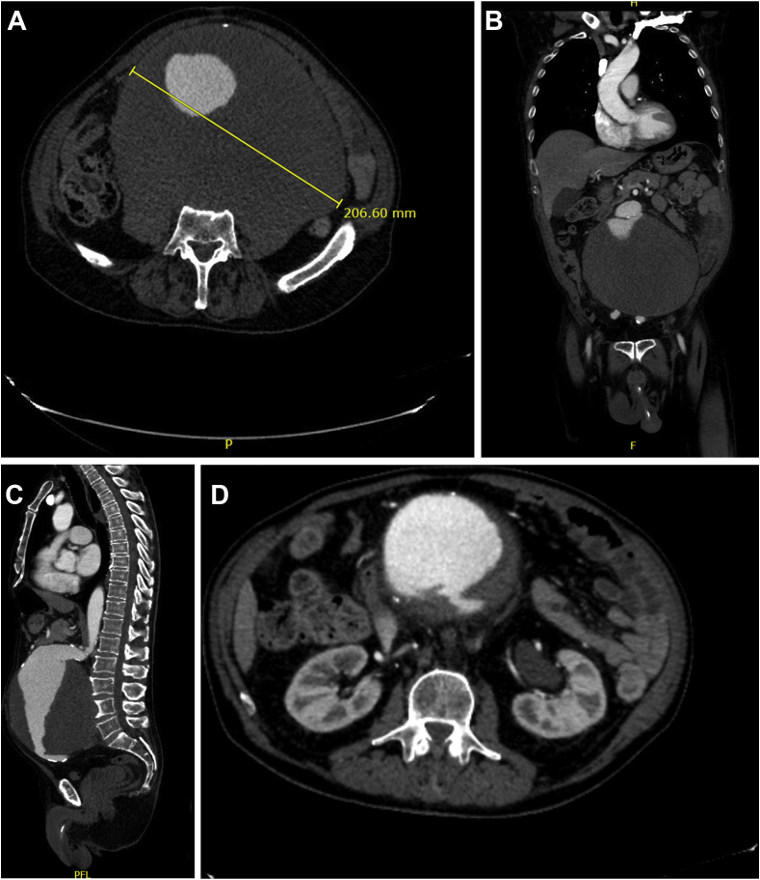

D- Aortic Aneurysm

CT scan for varying degrees of diverticular disease (1) diverticulum in the sigmoid colon (2) degree of diverticulitis present (3) abscess formation, secondary to ongoing diverticulitis